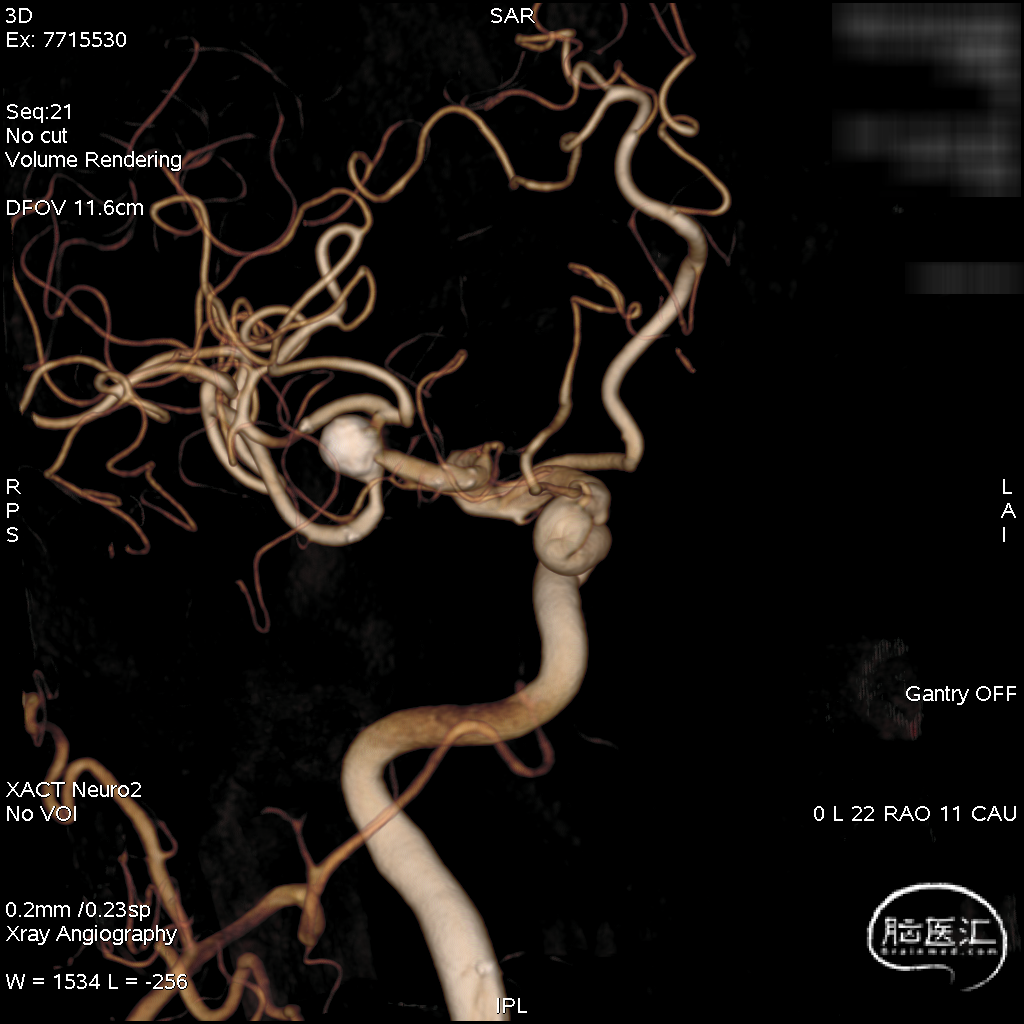

术前工作位与三维重建:显示右侧MCA分叉部未破裂动脉瘤,6.9mm*7.2mm,瘤颈7.4mm。该病例之困难在于M1迂曲成袢。

术后三维重建,支架贴壁良好,动脉瘤完全栓塞。